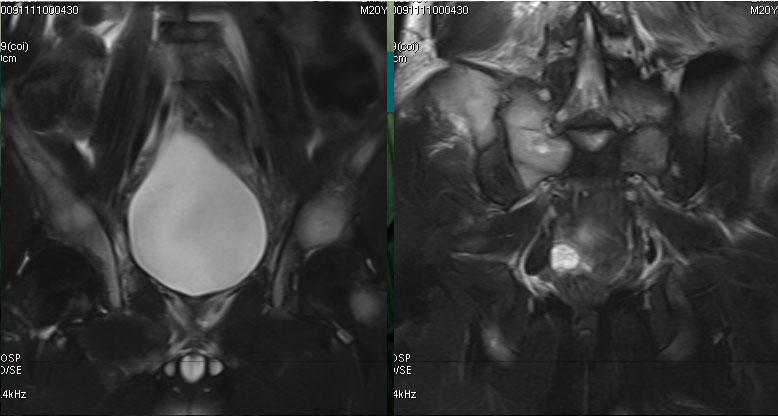

男性,20岁。

颈部疼痛2月,腰部臀部疼痛1月。

前臂肿物活检,病理报告:小圆细胞恶性肿瘤,免疫组化考虑为PNET/尤文氏肉瘤

On T1WI, the tumor demonstrated isointensity or slightly hypointensity; on T2WI, the tumor demonstrated heterogeneous hyperintensity.

The tumor demonstrated heterogeneous enhancement on contrast-enhanced CT/T1WI.

Cystic necrotic component and haemorrhagic change are usually obvious.